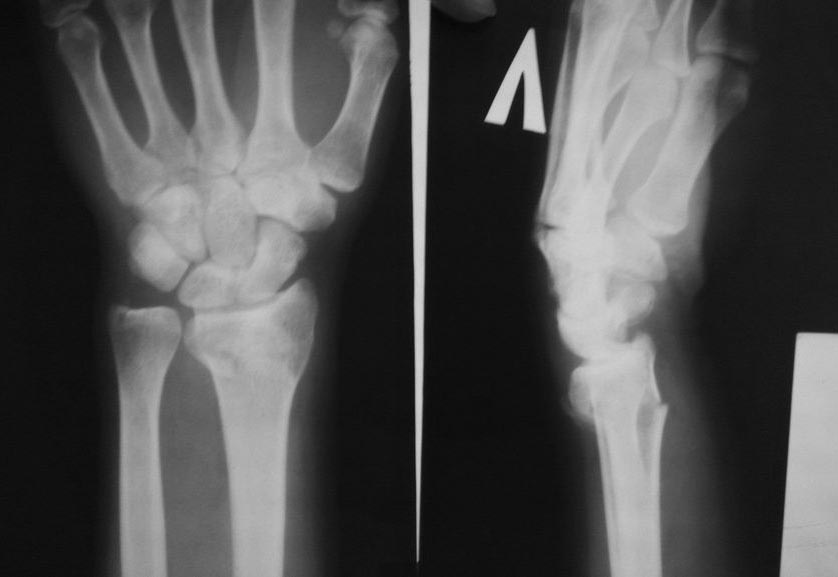

Добрый день. После консолидации перелома лучевой кости со смещением наблюдается нестабильность киста из-за подвывиха головки локтевой кости в тыльную сторону.

После консолидации перелома лучевой кости со смещением наблюдается нестабильность кисти из-за подвывиха головки локтевой кости в тыльную сторону.

Функционал кисти сгибательно-разгибательный, вращательный практически 100%, беспокоит слабость хвата. после снятия гипса была контрактура в кистевом суставе, за 2-3 недели руку разработал. в марте 20 числа прощупывал запястье и головка локтевой кисти подвывихнулась.

Рентгенограммы прикладываю.

Рентгенограммы в таком порядке:

1. 2 января 2014 перелом

2. 2 января 2014 контроль после в репозиции в гипсе

3. 9 января 2014 контроль

4. 29 января 2014 снятие гипса

5. 28 марта 2014 после вывих прямая проекция

6. 28 марта 2014 после вывих боковая проекция